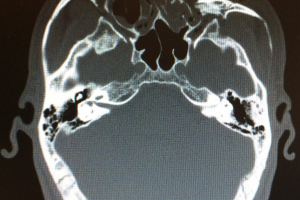

Traumatologia MXF